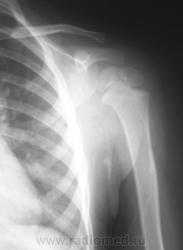

Пол пациента: Мужской пол Тип патологии: Травма Область исследования: Скелетно-мышечная система Методы исследования: Rg Ребенок доставлен по «ургенту». Травма. Направлен на рентгенографию левого плечевого сустава. https://radiomed.ru/sites/default/files/styles/case_slider_image/public/user/12/2.p1190014a.jpg?itok=1gdJVd7R https://radiomed.ru/sites/default/files/styles/case_slider_image/public/user/12/3.p1190015.jpg?itok=J2sCFP2r https://radiomed.ru/sites/default/files/styles/case_slider_image/public/user/12/4.p1190015a.jpg?itok=J9XWCaEU ID:11399 Ср, 19/01/2011 - 17:41 #1 Катенёв Валенти... Не на сайте Был на сайте: 7 лет 2 недели назад Зарегистрирован: 22.03.2008 - 22:15 Публикации: 54876 Для сравнения, дежурный хирург, попросил сделать правый плечевой сустав.Приложения: Ср, 19/01/2011 - 18:50 #2 Vega Не на сайте Был на сайте: 3 месяцев 1 неделя назад Зарегистрирован: 22.01.2009 - 19:16 Публикации: 1087 Перелом левой ключицы Ср, 19/01/2011 - 19:22 #3 Ola-la Не на сайте Был на сайте: 10 месяцев 6 дней назад Зарегистрирован: 06.12.2008 - 09:33 Публикации: 1786 Может быть, если есть клиника, но немного сомнительно. А почему опять нет второй проекции? https://www.instagram.com/pediatricradiology/ Ср, 19/01/2011 - 20:11 #4 Катенёв Валенти... Не на сайте Был на сайте: 7 лет 2 недели назад Зарегистрирован: 22.03.2008 - 22:15 Публикации: 54876 Ola-la wrote: Может быть, если есть клиника, но немного сомнительно. А почему опять нет второй проекции? Ургент! Как дежурный врач требует, так лаборант и делает. Ср, 19/01/2011 - 21:25 #5 Ola-la Не на сайте Был на сайте: 10 месяцев 6 дней назад Зарегистрирован: 06.12.2008 - 09:33 Публикации: 1786 А у нас дежурные требуют всегда в двух проекциях. https://www.instagram.com/pediatricradiology/ Ср, 19/01/2011 - 21:54 #6 Катенёв Валенти... Не на сайте Был на сайте: 7 лет 2 недели назад Зарегистрирован: 22.03.2008 - 22:15 Публикации: 54876 Ola-la wrote: А у нас дежурные требуют всегда в двух проекциях. Сравнили! У Вас, кто дежурит? А, у нас кто? Ваши, что-то хоть сделают, а наши в основном наблюдают...с определенного расстояния.

Для сравнения, дежурный хирург, попросил сделать правый плечевой сустав.